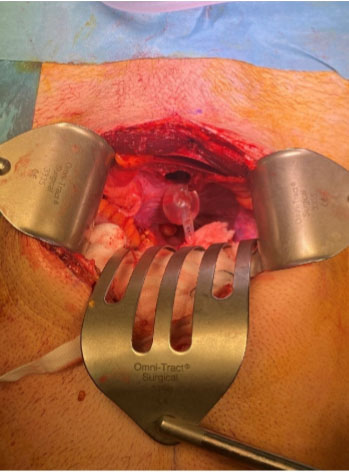

Intraoperative findings included a large volume of intraperitoneal urinoma with minimal blood staining. Evacuation of the urinoma revealed inflamed but viable small bowels and an approximately 4 cm laceration in the dome of the bladder (Figure 3 and Figure 4). Inspection of the bladder internally via the defect was generally normal. The laceration was repaired with a double layer closure with vicryl 2.0. A leak test was performed with 420 mL of normal saline injected through the urethral catheter after the repair and no further extravasation was noted. A small amount of inflammatory matrix was noted in the intra-peritoneal cavity which was washed out with 2 liters of warm normal saline. The abdomen was then closed in a single layer with two loops PDS. A Robinson’s drain was placed in the pelvis. The 14 French urethral catheter was replaced by an 18 French one.

Figure 3: Intra-operative finding of an intraperitoneal bladder rupture at the dome.

Share Image:

Figure 4: Inflated catheter balloon with 10 mL of water passing easily through intraperitoneal bladder rupture.